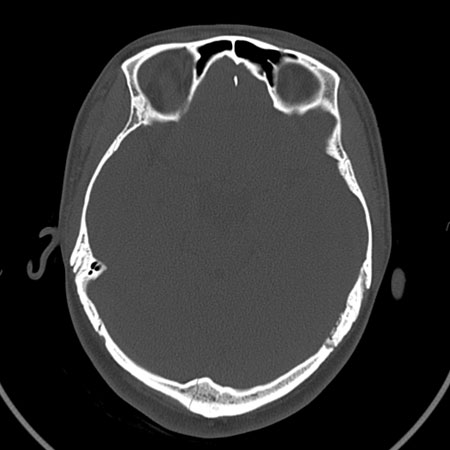

请问各位战友:图示箭头处是否为颅骨骨折?

病史:患者,女,20岁.头部及腹部外伤20分钟.伤后昏迷,无呕吐.头及右侧腰背部疼痛,双侧瞳孔等大,

右肾区叩痛.其它无异常.患者家属否认原有外伤史.

请大家看看是否为颅骨骨折.还是正常变异,或为陈旧骨折.谢谢.

枕骨的线样低密度影锐利、清晰,但正好位于矢状缝的位置,局部无明显软组织肿块,相临及对冲部位脑实质亦无出血及挫裂伤表现。

单就这几层暂不考虑骨折,建议上传完整图片。

未见异常。

枕骨骨折,另外一处不考虑骨折

绝对不是新鲜骨折!!!!

考虑正常变异!!

枕骨线样低密度影,不排除骨折

未见明显骨折征象。